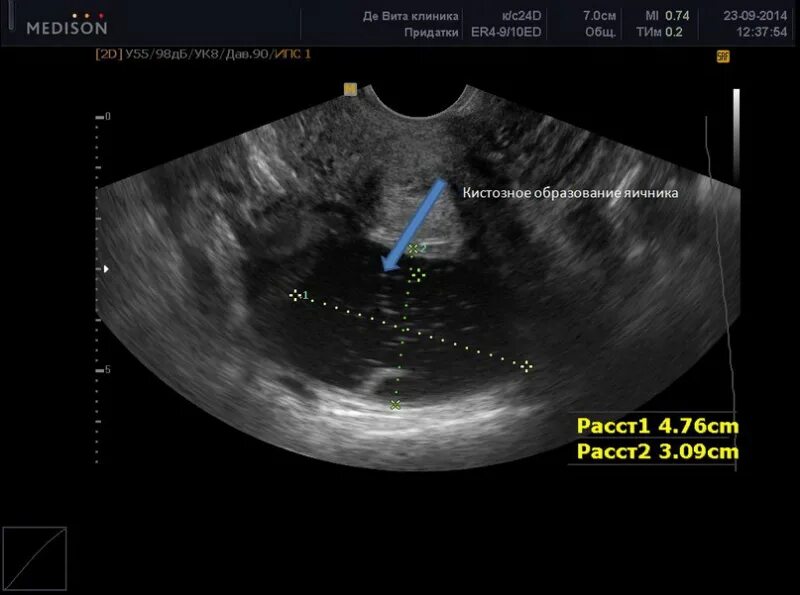

Когда делать узи яичников